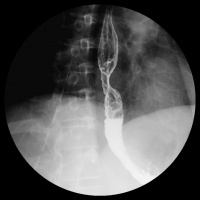

- X线食管钡餐检查:此为最基本的常规检查。此法检查简单、无痛苦、符合率高。检查可观察食管的蠕动状况、管壁的舒张度、食管黏膜改变、食管充盈缺损和梗阻程度。食管蠕动停顿或逆蠕动,食管壁局部僵硬不能充分扩张,食管黏膜紊乱、中断和破坏,食管管腔狭窄,不规则充盈缺损、溃疡或瘘管形成及食管轴向异常等均为食管癌的重要征象。低张双重造影对早期食管癌的检出较常规造影更有效。